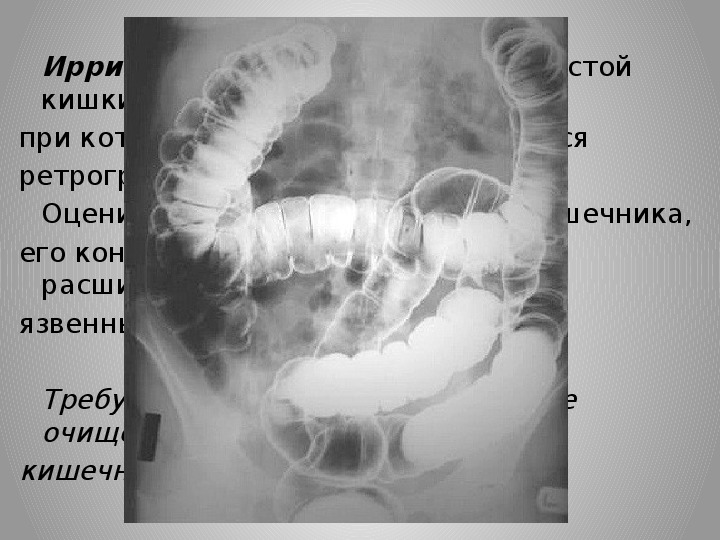

Участие сестры в инструментальных методах исследования Пациент должен знать цель и важность предстоящего исследования; Пациент должен представлять ход предстоящего исследования, субъективные ощущения; Пациент должен быть уверен в безболезненности и безопасности; Пациент должен знать весь объём предшествующих мероприятий и их важность. Изобретатель данного метода Вильгельм Конрад Рентген (1845-1923) – немецкий физик-экспериментатор. R-исследование основано на свойстве лучей, в различной степени, проникать через ткани Организма и при попадании на фотографическую плёнку, разлагает бромид серебра и вызывает появление фотографического изображения.